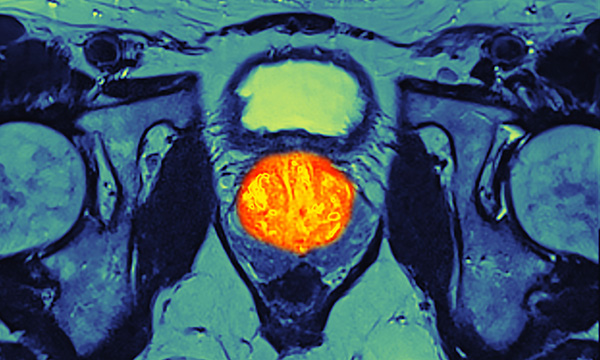

Study shows overall hazard from external beam radiotherapy and brachytherapy remains low.